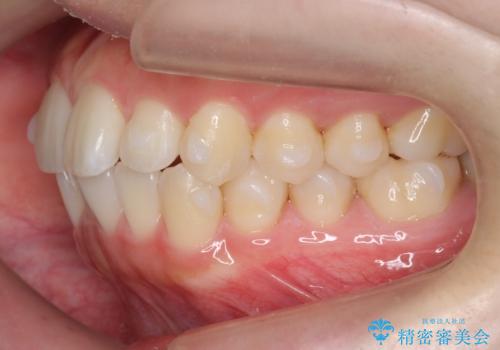

インビザライン モニターで前歯をきれいに

- 前歯のがたつきをきにされていました。

上下の前歯をやすりがけする処置(IPR)を行い、前歯の並びを出っ歯にしないようにしながら整えました。

症状が軽度であるためモニター採用になりました。